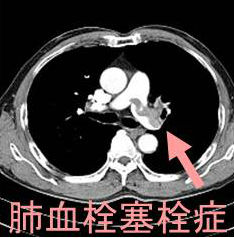

肺血栓塞栓症(肺梗塞)はエコノミー症候群(エコノミークラス症候群)として有名ですが、抗リン脂質抗体症候群でもおこります[Open Access Maced J Med Sci. 2015 Dec 15;3(4):705-9.]。

- 胸部造影CTでほぼ確定